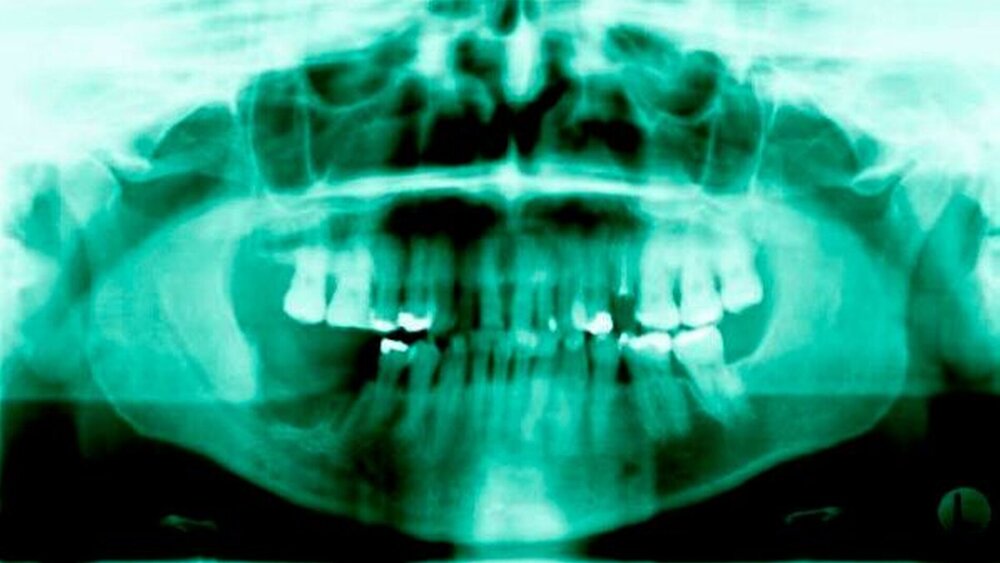

Die Zähne 46 und 47 erwiesen sich als asensibel. Die radiologische Untersuchung (Orthopantomogramm (siehe Abbildung 1b) und digitale Volumentomographie) zeigten gemischt radioluzente und radioopake Areale in regio 46/47 in unmittelbarer Nähe des Canalis mandibulae rechts.